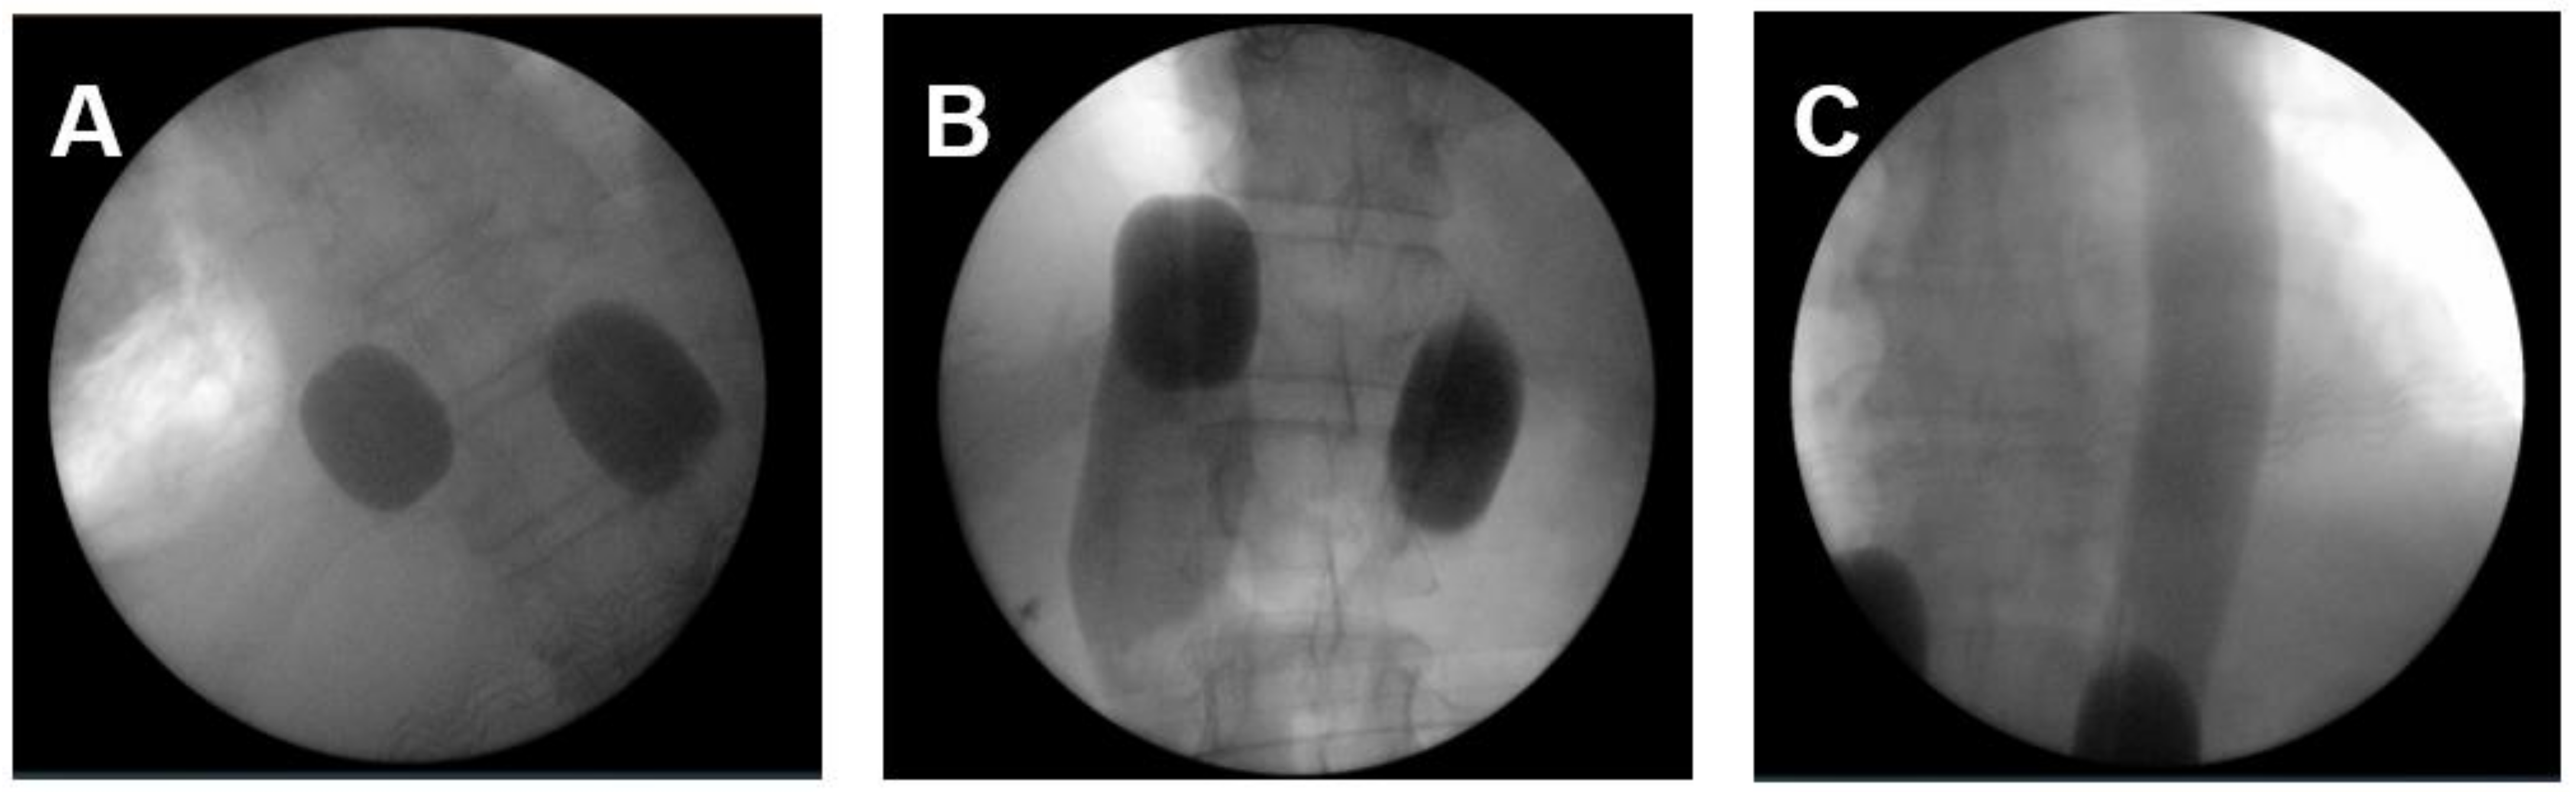

The applied perfusion techniques have been described in detail previously [14,19,20]. To address the primary tumor, mediastinal, lung and cervical metastases an ITP was performed. In total 36 ITPs were conducted. Briefly, RegCTx was performed under general anesthesia and full systemic anticoagulation with heparin. An approximately five cm incision was placed in the groin region and the femoral vessels explored. The vessels were looped with vessel-loops and a venous and arterial three-channel stop-flow balloon catheter was inserted in the inferior vena cava and aorta. Cava catheter was blocked beneath the right atrium, and the aorta was blocked slightly below of the diaphragm plane. Placement was undertaken only under X-ray control. Correct placement of the catheters was documented by cavography and aortography, respectively (Figure 1A–C). The upper arms were blocked by pneumatic cuffs ensuring the isolation of the chest, head, and neck area. Chemotherapy was applied manually with high pulsatile pressure against the aortic blood stream through the coaxial channel of the arterial balloon catheter.

Figure 1.

The intraoperative pictures demonstrate (A) placement of balloon catheter and level of blockage in the inferior cava vein and aorta; (B) blood flow stop below the right atrium from downwards and depiction of inferior cava vein and hepatic veins; (C) blood flow stop below the inflated balloon catheter in the aorta and depiction of covering entire thoracic aorta with pulsatile injections.